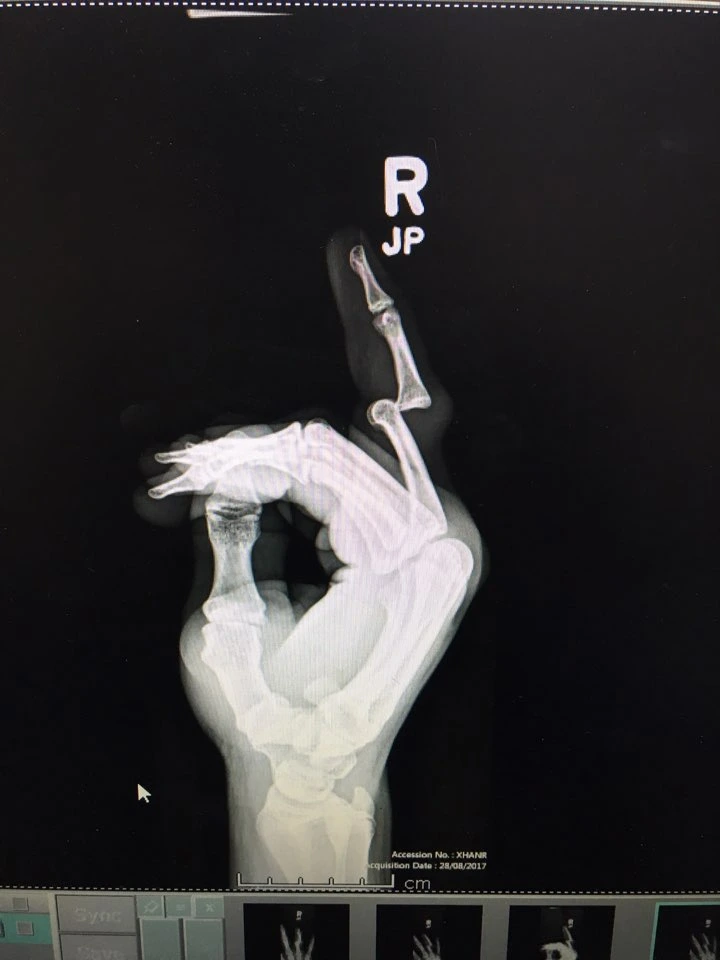

저렇게 감기 걸렸다 했는데 죽는 경우가 있는가 하면 공수 훈련하는 특전사 중 하나는 낙하산이 안 펴져서 나무 위에 떨어졌는데 뼈 하나 부러지고 살 있어. 정신 나간 훈련병 중 하나는 군대에 있느니 자살하겠다며 건물 3층에서 뛰어내렸거든. 근데 뼈 하나 안 부러진 거야. 멀쩡해서 그날 바로 본대 복귀했어. 내가 머리부터 발가락까지 엑스레이 찍었는데 멀쩡하더라니까.